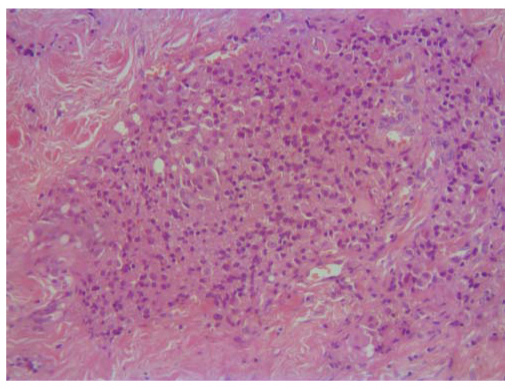

2. Fig. 2. The results of histological examination. Another part of the tumor of the thyroid gland with the presence of pseudopapillary structures (× 20).